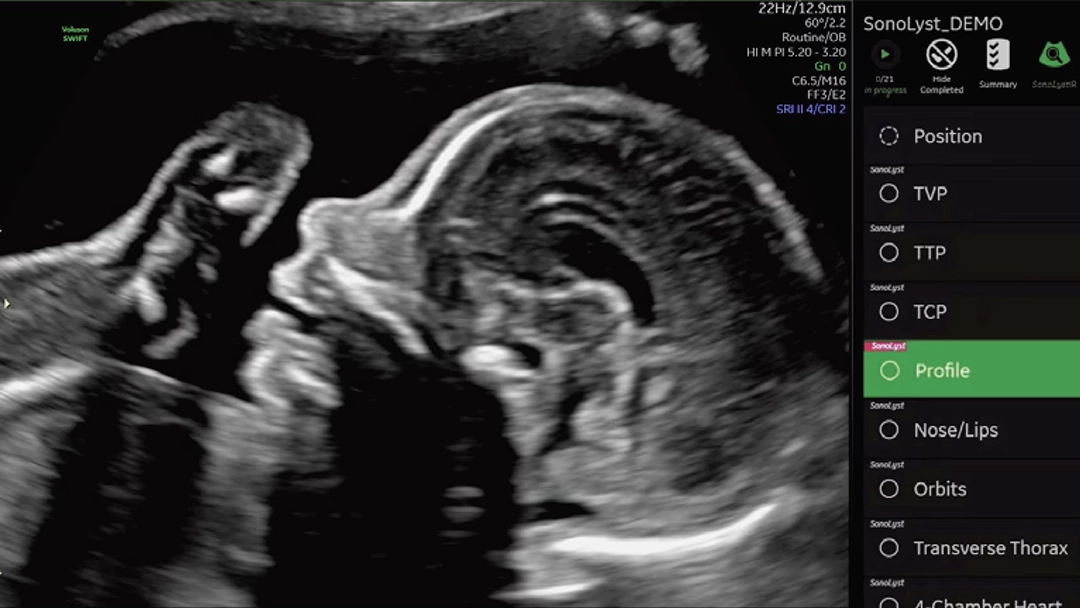

Identifica anatomía automáticamente y ayuda en etiquetado y mediciones.